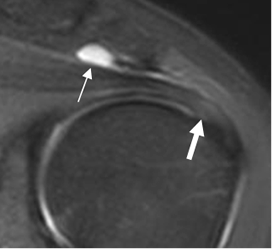

Fig 143. Bursitis subacromial.

RM coronal en STIR. Colección a nivel subacromial, por bursitis. (Flecha delgada). En tendón del supraespinoso es hiperintenso, por tendinitis asociada. (Flecha gruesa).